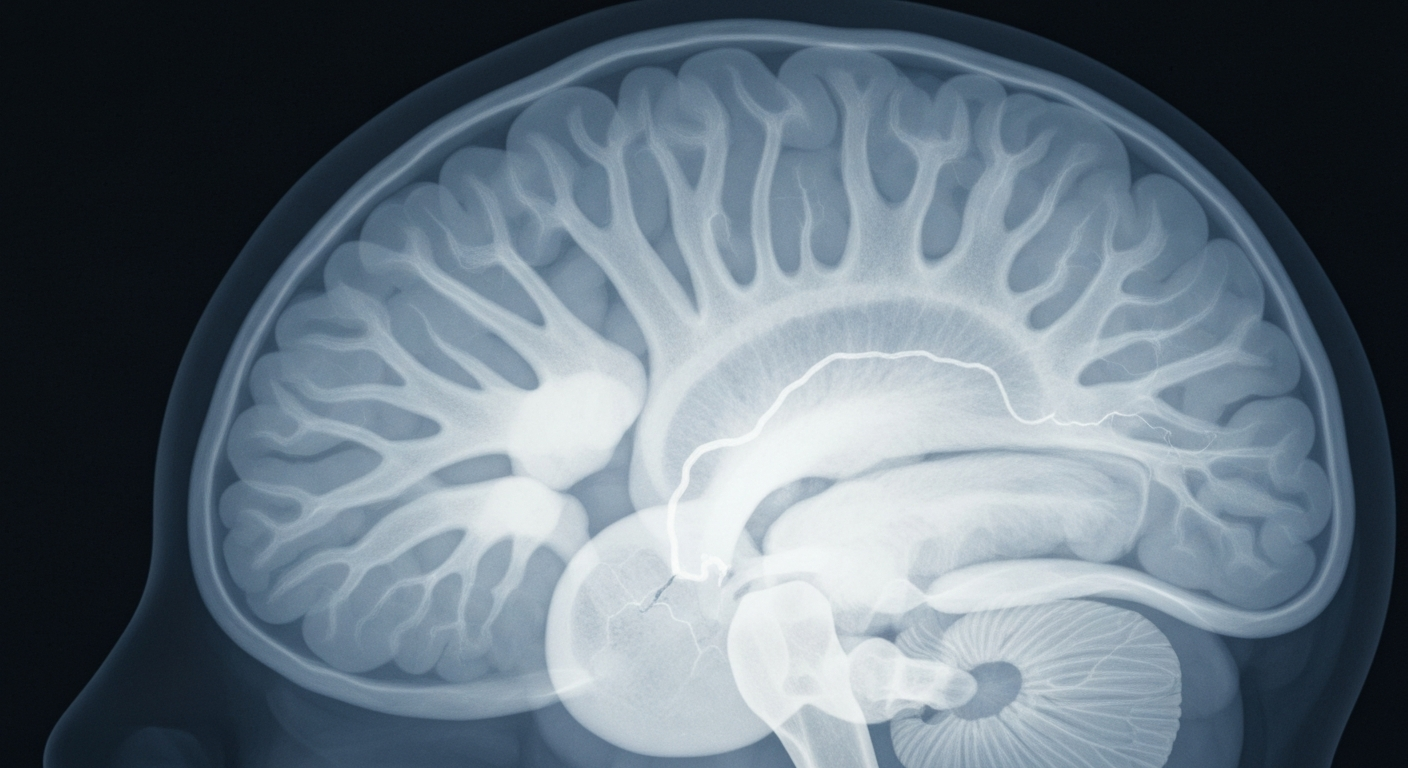

An X-ray view into the inner workings of the brain reveals the impact of a stroke, as 'Dr. Pimple Popper' Sandra Lee recovers from a health scare.Upland TodayDr. Sandra Lee, the reality TV dermatologist and surgeon known as 'Dr. Pimple Popper', suffered an ischemic stroke last November while filming her show. Lee, 55, said unmanaged cholesterol levels and high blood pressure were likely contributors to the stroke, plus the stress of balancing her medical practice with the demands of her TV show. After spending two months in physical and occupational therapy, Lee has returned to production and is preparing to debut new episodes of 'Dr. Pimple Popper' on Lifetime.

Lee said she experienced what she thought was a 'hot flash' while filming new episodes of her show at her Upland, California office. That evening, she experienced shooting pains in one leg and trouble navigating stairs. The next day, she had slurred speech and weakness on her left side. An MRI revealed she had suffered an ischemic stroke, where a vessel supplying blood to the brain becomes obstructed. Lee spent two months in physical and occupational therapy working to regain function in her left hand and improve her balance and movement before returning to production in January.